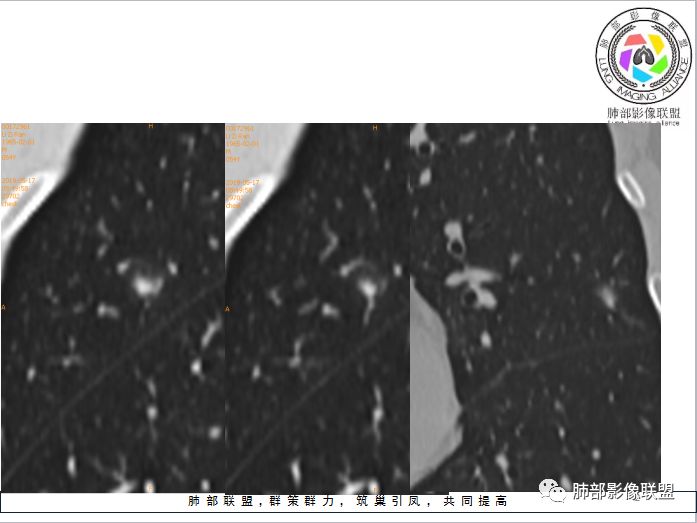

患者中年男性,体检发现。查肿瘤标志物、结核菌素实验、肝肾功能无明显异常。胸部CT:左肺上叶胸膜下类圆形实性结节,可见分叶、平直及血管贴边征象,周围可见磨玻璃影。综合考虑良性病变,隐球菌可能大,鉴别腺癌。

中年男性,平素体健,无呼吸异常主诉及体征,查血无明显异常。体检发现左肺上叶实性类圆形结节影,部分层面周围有磨玻璃晕症,可见血管进入,考虑良性,考虑炎性肉芽肿,考虑隐球菌感染可能,需与腺Ca、PSP鉴别

左上肺结节,边缘有晕,部分边缘清,部分模糊,无收缩力,贴血管边缘平直,考虑隐球菌可能 ,鉴别粘液腺癌。

左肺上叶结节,边缘光滑清晰,部分边缘平直,周围有晕,血管贴边,考虑炎性肉芽肿,隐球菌。鉴别浸润腺癌。

左肺上叶结节,轻度分叶,滋养血管征,晕中软毛刺,边缘偏模糊,考虑隐球菌,鉴别诊断黏液腺癌,晕偏一侧边缘偏清楚。

中年男性,左肺上叶类圆形实性结节,浅分叶、部分边缘平直,血管增粗贴边通过,周围晕征。实验室检查不支持结核,考虑炎性肉芽肿,隐球菌,鉴别腺癌。